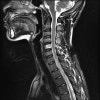

MRI : 염증 조직의 파급 정도를 알기 쉽습니다.

MRI : 척추 결핵(Spinal tuberculosis)

MRI : 척추 결핵(=Tuberculous spondylitis with large prevertebral abscess)